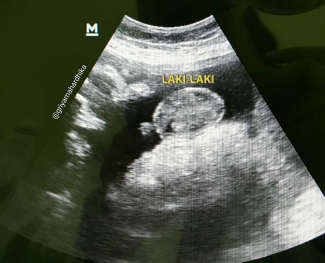

Agar tahu jenis kelamin bayi Anda biasanya disarankan untuk melakukan USG pada usia kehamilan 18-22 minggu. Hamil 37 Minggu Belum Ada Tanda-tanda Melahirkan. GA Gestational Age.

Ini karena sampai usia 14 minggu kehamilan biasanya bayi laki-laki dan perempuan belum bisa dibedakan pada hasil USG. Karena dokter saya saat itu bilangmgkin anak saya nanti lahirnya pendek. Ini biasanya jadi hal yang ditunggu-tunggu oleh banyak pasangan ketika mempelajari cara membaca hasil USG kehamilan.

Usia kandungan Minyu sudah mencapai 37 Minggu. Biasanya ketika bunda melakukan pemindaian di kehamilan 18-20 minggu ini adalah titik di mana waktunya Anda bisa mengetahui jenis kelamin bayi dengan USG. Biparietal diameter BPD is one of many measurements that are taken during ultrasound procedures in pregnancy.